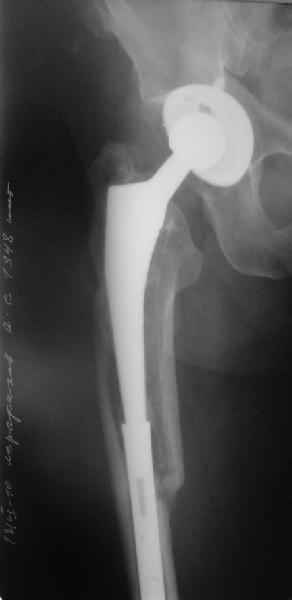

Пациента удалось осмотреть недавно. Достигнутый результат сохраняется. Перелом бедра сросся. Конечность опорная и безболезненная, ходит без трости. Ножка, похоже, реинтегрировалась, как и надеялись. Снимки и фото в приложении. Комментарии приветствуются.

Надо ли что-то делать дальше, как полагаете? Убрать винты? Убрать "удлинитель ножки"? Или оставить все, как есть? Спасибо заранее.